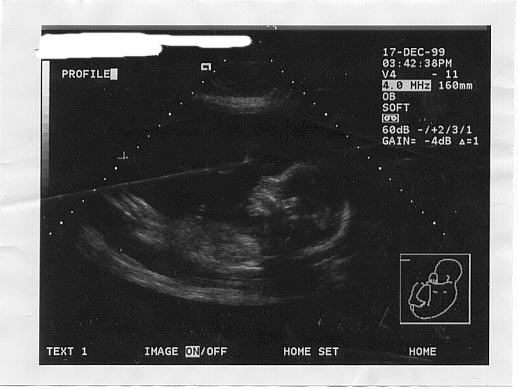

19 weeks 4 days

She is 13.5 ozs & 9 inches long